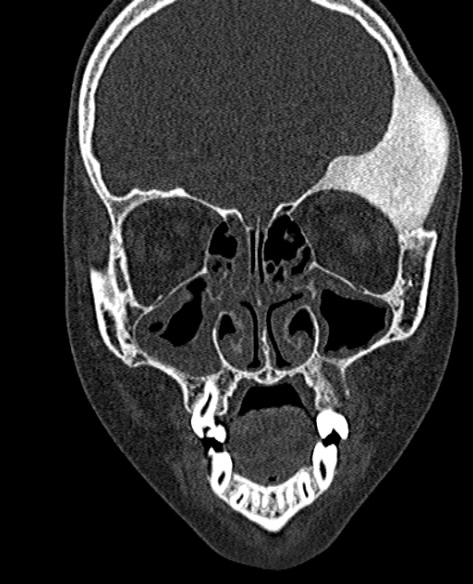

Welche Befunde erheben Sie auf dem vorliegenden Schädel-CT eines 10-jährigen Mädchens? Welche Diagnose ist am wahrscheinlichsten?